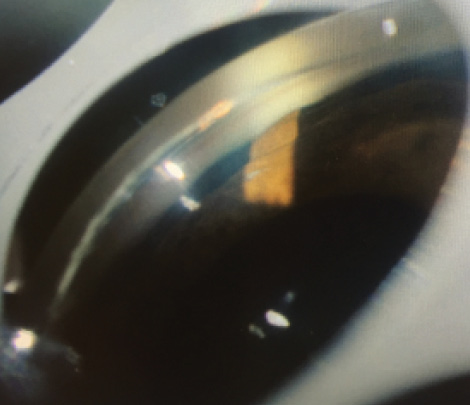

Standard automated perimetry by Swedish Interactive Thresholding Algorithm (SITA) testing demonstrated preserved field in the right eye and a cecocentral defect in the left eye. Ultrasound biomicroscopy (UBM; Figure 2) demonstrated cystic areas within and around the ciliary body, shallow anterior chambers with closed angles, and a plateau iris configuration in both eyes. Peripheral iridotomy was patent in the right eye and not visualized in the left. Anterior segment OCT (Figure 3) demonstrated closed angles consistent with gonioscopy and UBM findings.

Figure 3. Anterior segment OCT demonstrated closed angles consistent with gonioscopy and UBM findings.